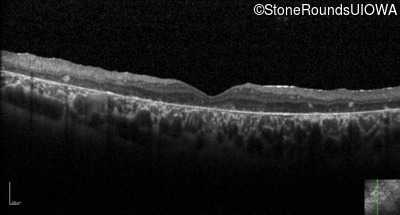

Optical Coherence Tomography - Right - 20/200 sc

Exemplar / OCT Stack